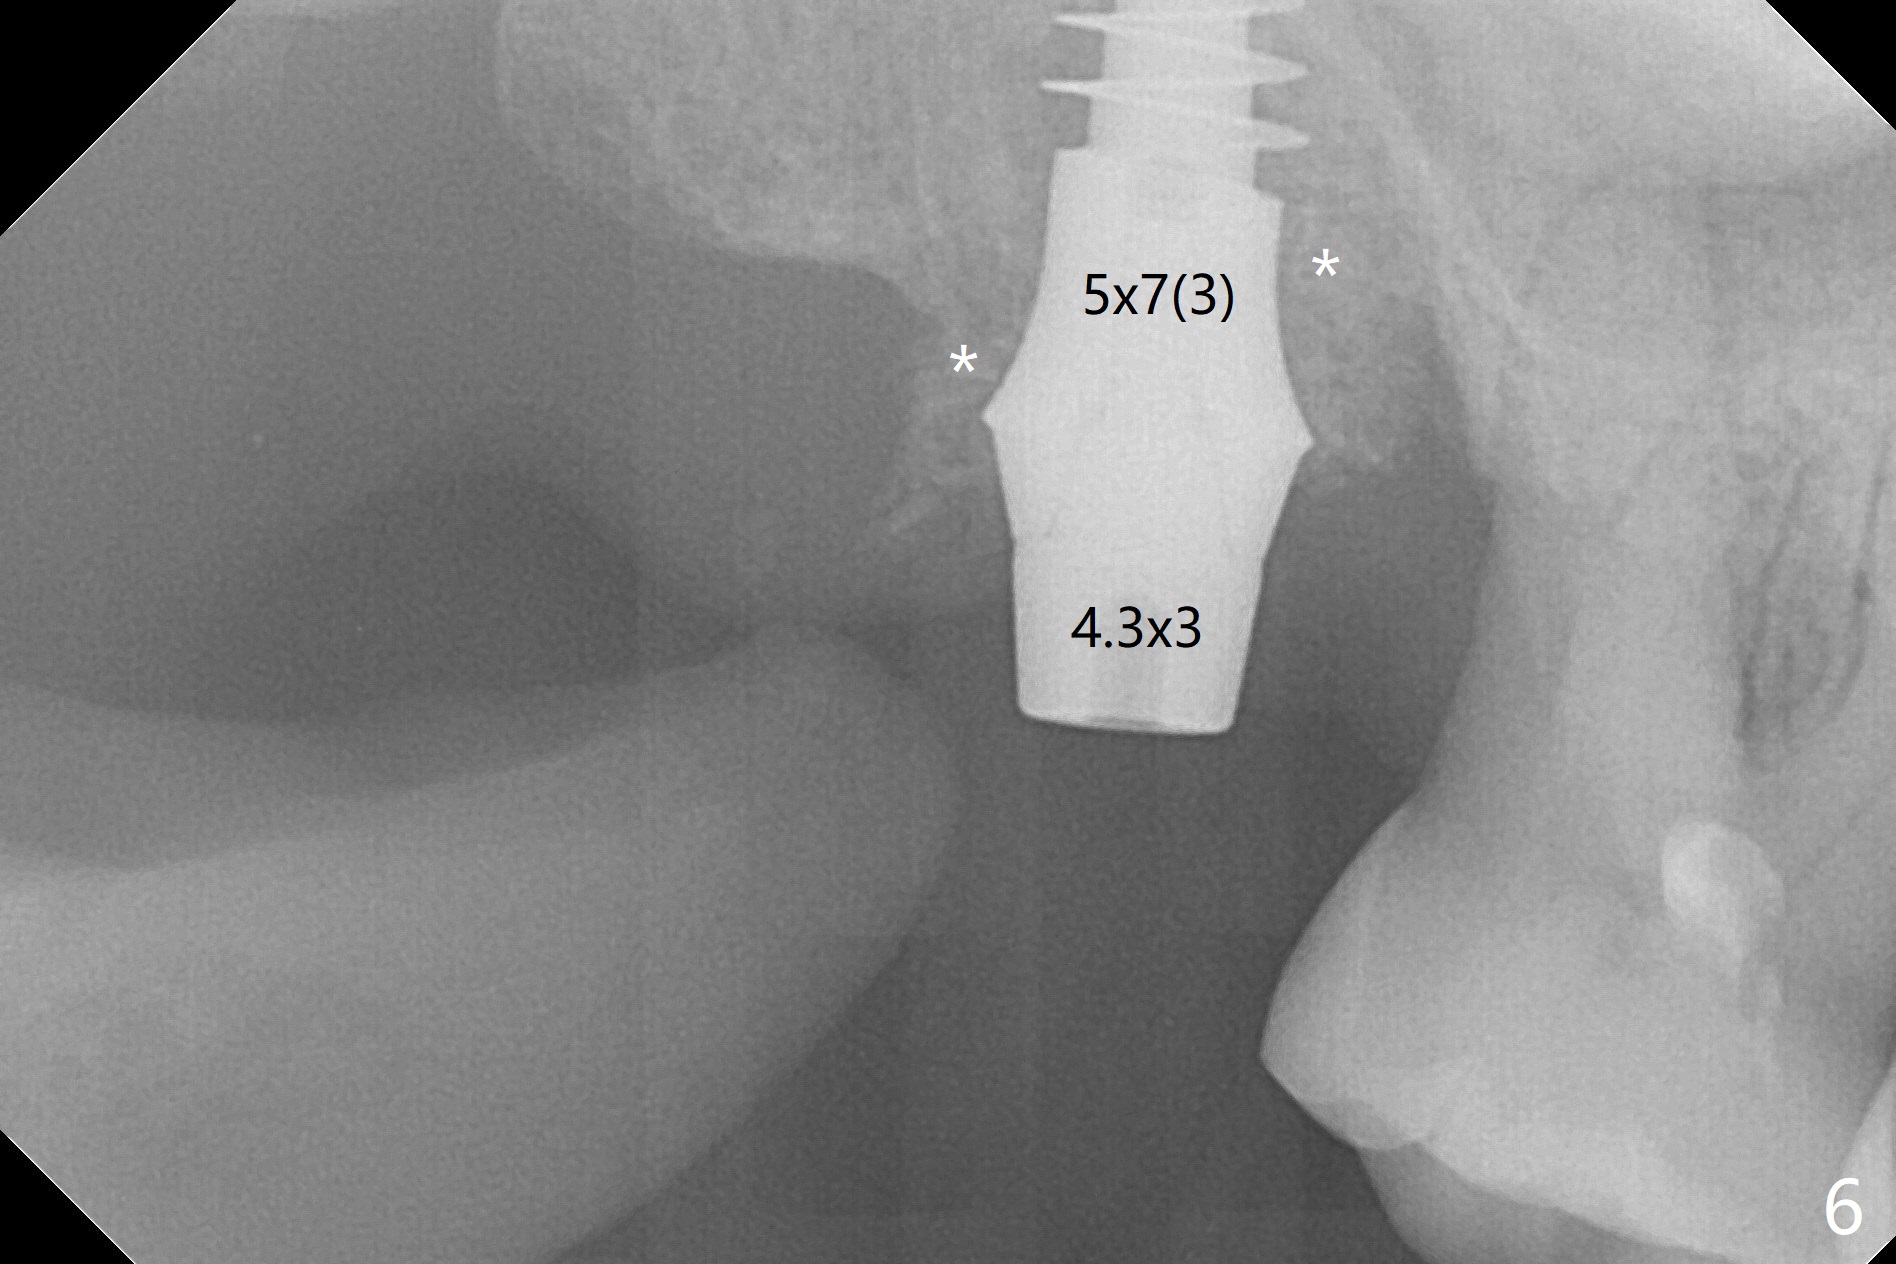

After extraction of the tooth #2 (Fig.1), osteotomy is supposed to be initiated in the mesial slope (Fig.2 arrow). With Magic Expanders (3-4.8 mm), osteotomy ends up in the bottom of the socket (Fig.3). Trajectory is found to be off when 4x9 and 5x9 mm dummy FC implants are placed with stability (Fig.4,5). The final implant, Magicore (5x7(3)mm, >29 Ncm), appears to be placed too deep for restoration (Fig.6,7); a screw retained crown may be a solution. PRF membrane and Vanilla (allograft) are used for sinus lift (no sinus membrane perforation). Following Vanilla graft in the socket gap (Fig.6 *), another piece of PRF membrane is used to cover socket opening. The membrane is fixed in place with suture and periodontal dressing. The implant seems to have osteointegrated 3.5 months postop (Fig.8). After change to 4.3x5 mm solid abutment and mesial surface adjustment, impression is taken for early loading because of removal of #14 implant. In fact the patient is satisfied with mastication improvement at #2 later on.